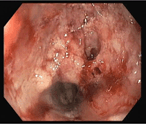

Ascaris lumbricoides and its almost deadly complication

Gabriel Alejandro Molina and others

Journal of Surgical Case Reports, Volume 2018, Issue 10, October 2018, rjy262, https://doi.org/10.1093/jscr/rjy262